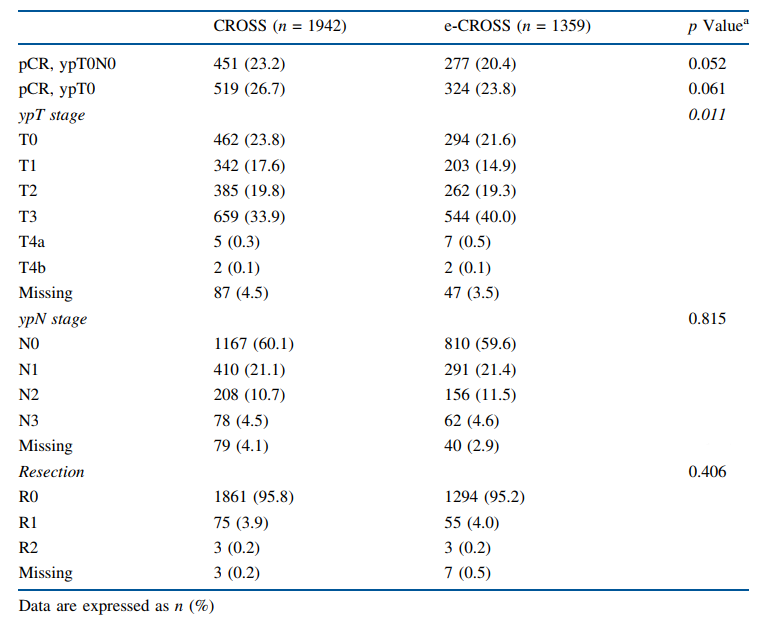

“食管癌文献月评”系列由【百济医学部】与【肿瘤资讯】共同推出,旨在分享食管癌领域的最新研究进展,更好助力临床诊疗。近期,一项发布于Ann Surg Oncol的研...

对于有手术切除机会的局部晚期食管癌患者来说,指南推荐术前应用新辅助治疗,目的是为后续的手术创造更佳的操作条件、减少手术创伤等,从而使患者获益。在新辅助更优方案的探...